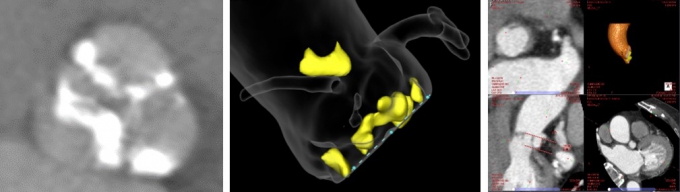

高精細なイメージングモダリティを総合した評価

当院では、安全性の高い治療を提供するために、CTやエコーによる精細な画像解析と検討を行っています。

心臓CT

TAVIを行う際、アプローチ可能な部位を評価します。胸部から骨盤までの大動脈の性状や蛇行の有無、心臓の位置と胸郭の関係を明瞭化することが可能です。また、詳細に大動脈弁の石灰化分布や弁輪サイズを計測し、人工弁の至適なサイズを判断します。